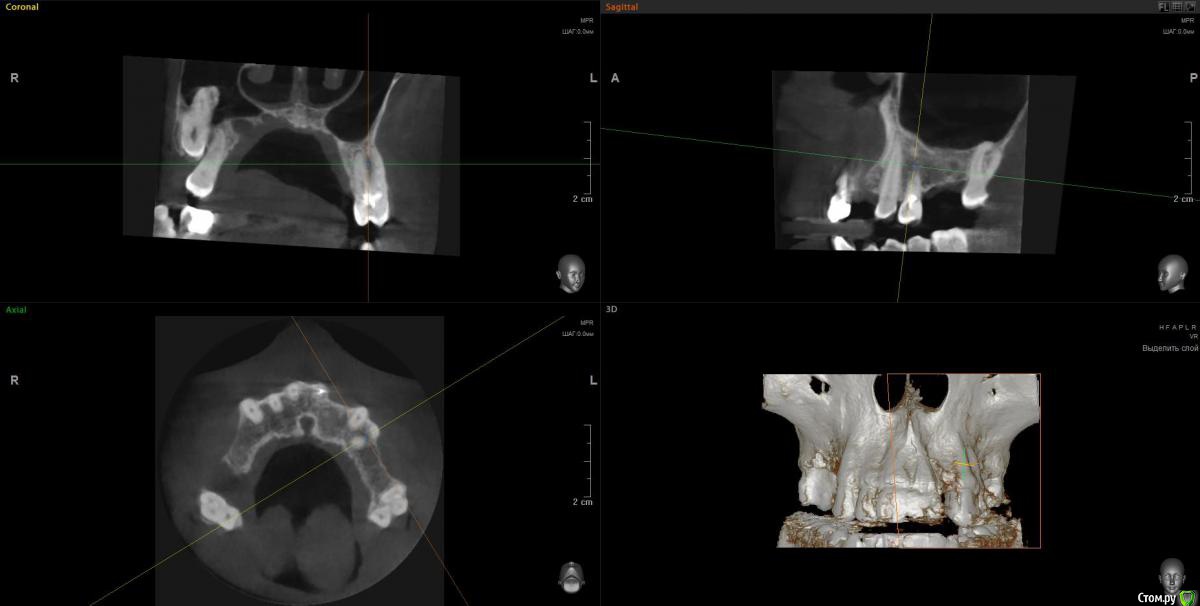

Просьба ко всем не равнодушным! Глянуть КТ верхней челюсти, 27 зуб  и место где удалили 16, может ещё где-то могут быть проблемы.  На фото видно где покраснение на дёснах, в этих местах возникают боли при движении головой. Бывает боль слева если засыпаю на левой стороне. Набуханий или флюсов нигде не видно.Прошу делиться мнениями, для меня это очень - очень важно. Стоматолог визуальных проблем на месте удалённого зуба не видит, всё зажило.

По данным КТ в зоне удалённого зуба 16 ничего особенного, разве что, ретенированный (непрорезавшийся) зуб 18.

Зуб 27 требует внимания, необходим очный осмотр.

Также стоит обратить внимание на зубы 21 и 24